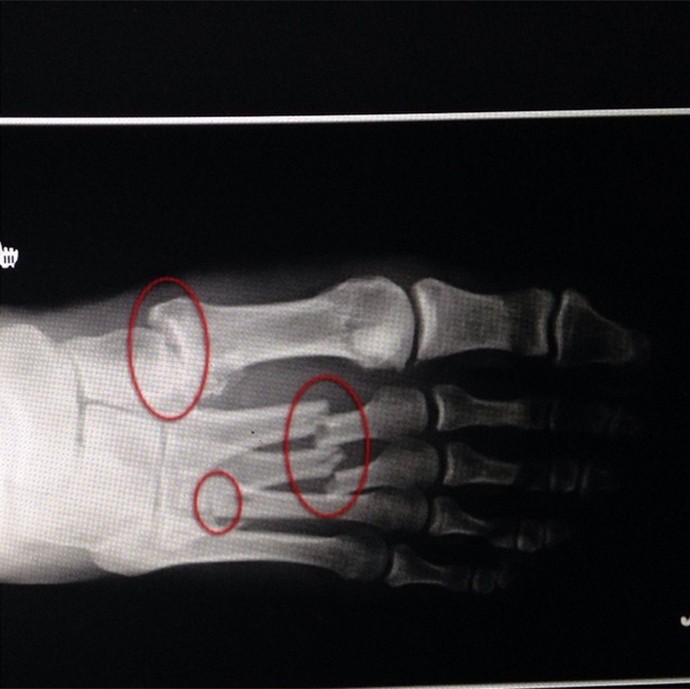

Midianews Apos Um Exame De Raio X Homem Descobre Verme Africano Em Seu Pe

Midianews Apos Um Exame De Raio X Homem Descobre Verme Africano Em Seu Pe from www.midianews.com.br